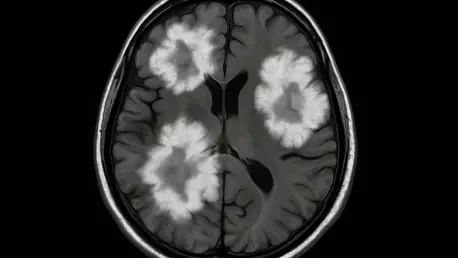

Magnetic Resonance Imaging (MRI) stands as the primary tool for detecting Tumefactive Demyelinating Lesions, though no single characteristic definitively identifies them, and understanding these nuances is critical for accurate diagnosis. Common findings include an incomplete or “open-ring” enhancement pattern after contrast administration, a relatively mild mass effect compared to the lesion’s size, and a tendency to spare the brain’s cortical gray matter. These traits help distinguish TDLs from tumors, which typically exhibit more pronounced mass effects and complete ring enhancement on scans. Understanding these radiological nuances is vital for narrowing down the differential diagnosis, particularly when clinical symptoms overlap with other neurological disorders. While MRI provides a foundational view, its limitations mean that additional methods are often necessary to build a comprehensive picture, especially in cases where the presentation is ambiguous or rapidly evolving.

Advanced imaging modalities, such as magnetic resonance spectroscopy (MRS) and perfusion-weighted imaging (PWI), offer deeper insights that enhance diagnostic precision for tumefactive demyelinating lesions (TDLs). In the case study under review, MRS revealed patterns indicative of demyelination rather than neoplasia, showing decreased N-acetylaspartate levels alongside elevated choline peaks. Similarly, PWI demonstrated reduced relative cerebral blood volume in the lesion area, a contrast to the elevated blood volume typical of tumors due to angiogenesis. These sophisticated techniques, while not universally accessible, provide critical data points that can tip the scales toward an accurate diagnosis. However, overlaps with other conditions persist, sometimes necessitating invasive procedures like biopsy when uncertainty remains. Combining multiple imaging approaches creates a more robust framework for identifying TDLs, reducing the likelihood of misclassification and ensuring that treatment aligns with the true nature of the condition.